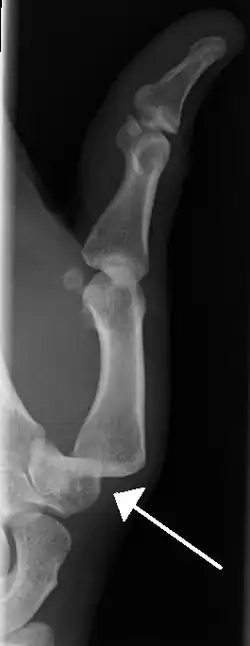

- Dislocation of the carpo-metacarpal joint.